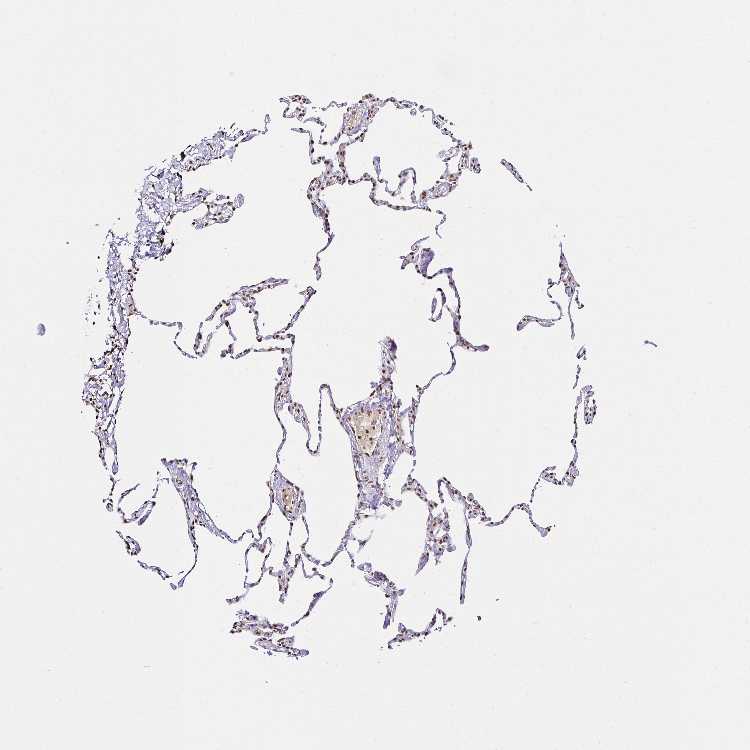

LUNG - Antibody stainingi

Antibody staining in the annotated cell types in the current human tissue is reported as not detected, low, medium, or high, based on conventional immunohistochemistry profiling in selected tissues. This score is based on the combination of the staining intensity and fraction of stained cells.

Each image is clickable and will lead to virtual microscopy that enables deeper exploration of all samples and also displays staining intensity scores, fraction scores and subcellular localization as well as patient and tissue information for each sample.

Antibody HPA062812

Alveolar cells High

Macrophages Medium